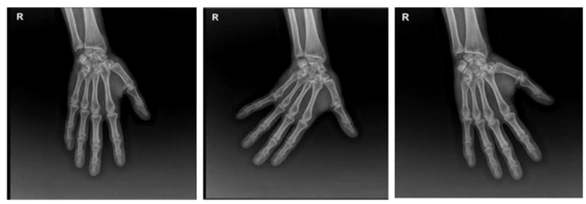

AD_4nXdoYvpyaHL_lkiM_jUuB1elGsfx5wjeoSsVIQWmePpS5AS8IF7SCgIZv2iLmhGNpVA_jRjra5JIIo8Rw4--YgWquNsOiFTQudax5T3SPAPkKR_Av9BkLslVsvOJ9zzEtqNRer9gyQ?key=0_7uFam0xD727dkPNLVHRw 그림2. 환자 엑스레이 사진

우선 방사선 촬영과 초음파검사를 시행하였습니다. 방사선촬영에서 일부의 관절간격이 변화가 있고, 초음파 검사에서는 정중신경의 단면적이 12mm² 로 부어 있는 손목터널증후군이 함께 있었습니다. 환자분의 치료는 손목과 손가락의 프롤로치료를 하고 정중신경의 신경유착박리술 (hydrodissection)을 시행하였습니다.